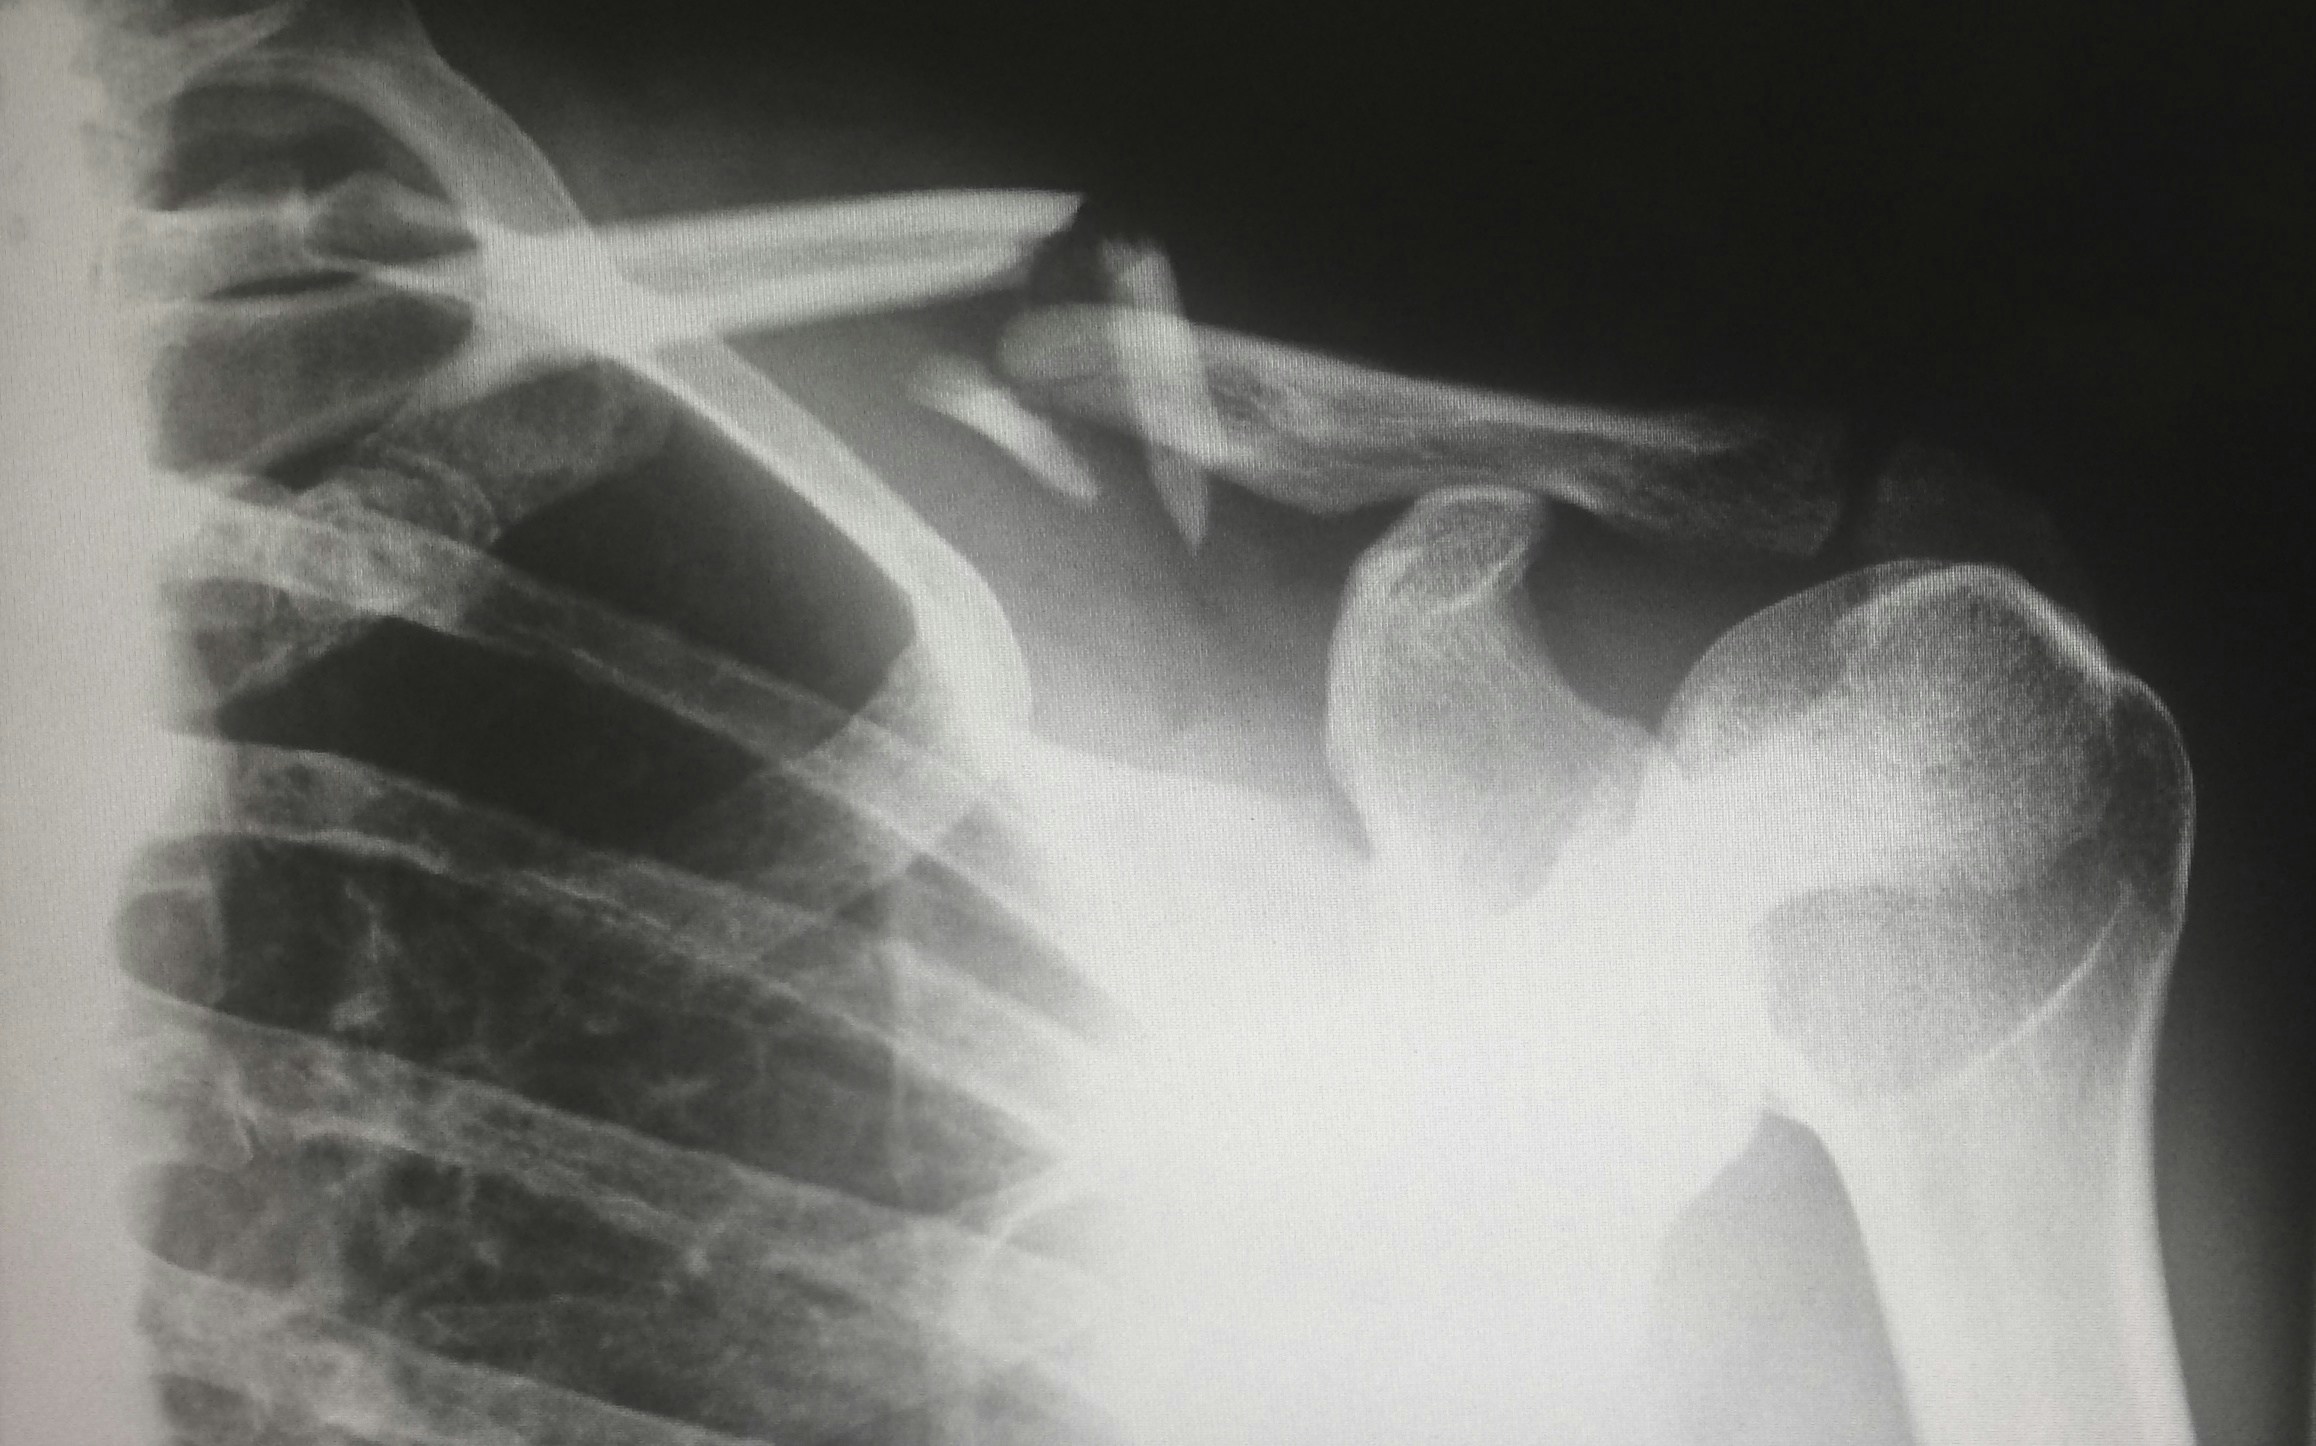

Serratus anterior pain is often diagnosed through a physical examination. The doctor will feel for tenderness or muscle spasms in the serratus anterior muscle. They may also ask the patient to perform certain movements, such as raising their arm over their head, to see if this causes pain. In some cases, imaging tests such as X-rays or MRI scans may be ordered to rule out other conditions that could be causing the pain.